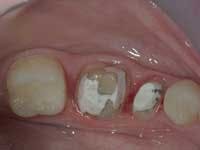

Less than one-half of the coronal tooth structure remaining (Figs. 1-6)

It is my opinion, regardless of the other factors present, that it is still advisable to place a post or posts in such teeth. Endodontically treated teeth with less than one-half of the coronal tooth structure remaining have a reduced chance of long-term service, and patients should be so advised as the treatment plan is developed.